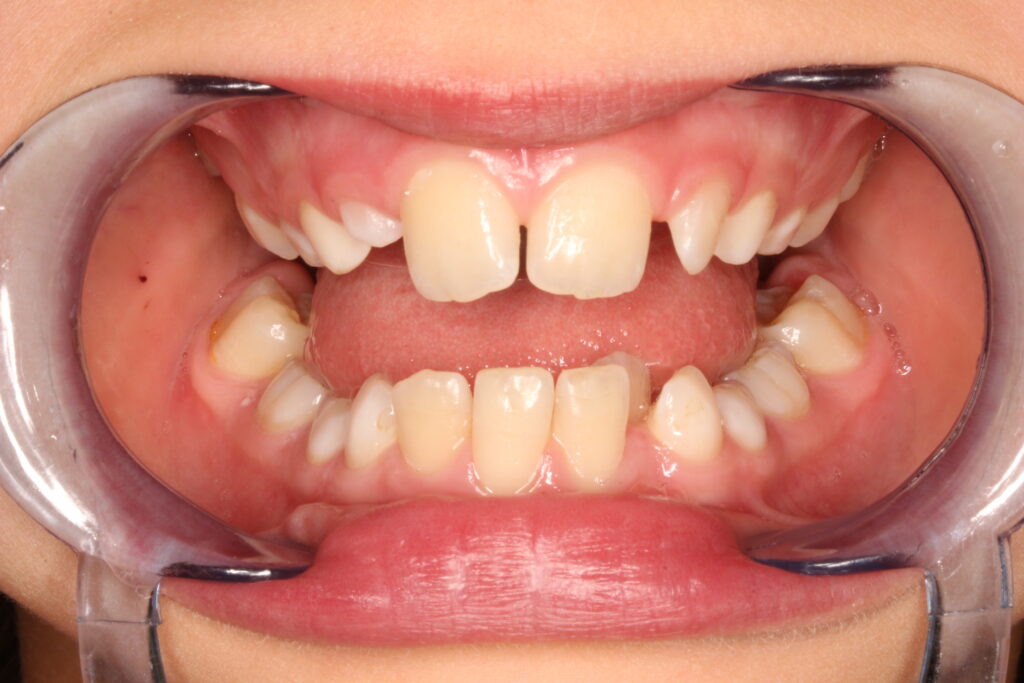

Az ALF készülék nem az agresszív erőhatásokra, hanem a funkcionális erők finom, biológiailag kíméletes irányítására épít. A klinikai tapasztalatok szerint ez tökéletes elég és mind a fogív fejlesztésében, keresztharapások megszűntetésében, helyteremtésben mind a nyelvtér növelésében jól működik.

A leggyakoribb a vegyes fogazat időszakában (6–11 év), de alkalmazható teljes tejfogazatban is nagyon korai kezelések esetében, akár 3-4 éves kortól is.